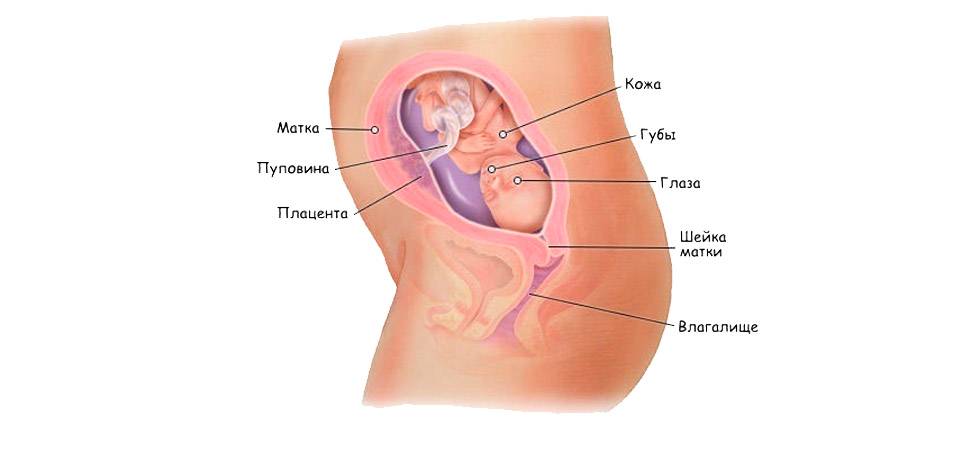

Что происходит с малышом на 22 недели беременности

- В этот период волосы малыша отрастают с особой интенсивностью, но их цвет еще не выражен – пока недостаточно меламина вырабатывает его маленькое тельце.

- Быстро развивается головной мозг. Именно в это время малыш начинает изучать себя и то, где он находится с помощью тактильных ощущений. Именно на 22 неделе беременности ребенок пробует шевелить пальчиками, касаться стенок плаценты и себя. Такое исследование ребенком пространства своего обитания будет усиливаться именно на 22 неделе, так что беременная мама будет хорошо ощущать его прикосновения.

- На стадии 22 недели ребенок в утробе матери останавливает свой рост в высоту. В дальнейшем происходит формирование рефлекторных мышц, они усложняются с каждым днем. Мозговые клетки уже почти сформировались, и мозг весит порядка 95 – 100 г.

- В этот период у ребенка начинается развитие желез внутренней секреции, в частности, потовых желез.

- Продолжают активно формироваться кости – кальций все больше накапливается и откладывается в организме младенца. В связи с этим беременным женщинам прописывают специализированные препараты, содержащие большое количество кальция.

- На 22 неделе беременности развитие позвоночника плода завершает свое формирование. К окончанию второго триместра все позвонки и межпозвоночные диски уже полностью образованы.

- Во время планового УЗИ на 22 неделе беременности на тельце малыша появляются еле заметные волосики, похожие на пух. Они формируют некий вакуум вокруг плода, задерживающий первородную смазку. Кроме этого, смазка защищает ребенка от соприкосновения с водной средой околоплодных вод. Непосредственно перед родами, волосики за ненадобностью исчезают, а предродовая смазка обеспечивает легкий выход малыша из утробы матери.

- Уже на 22 неделе ребенок должен шевелиться, подавая определенные знаки. Теперь уже это непросто проявления рефлекторной физической активности – это осмысленный анализ окружения и обстановки. В это время плод становится очень чувствительным ко всем внешним раздражителям, шуму, музыке разговору, свету и даже свежему воздуху. Теперь он уже непросто переворачивается и изучает окружающую его среду – он выражает свое недовольство или одобрение бурными движениями. Иногда, частое кувыркание младенца в утробе может свидетельствовать о недостатке кислорода, поэтому мамочке нужно трепетно прислушиваться к знакам и вовремя на них реагировать. Но не стоит перебарщивать, воспринимать любое движение ребенка в качестве недовольства или желания. Во время сна, а это большая часть времени, малыш не активен. Зато утром и вечером может разводить бурную деятельность. Проблема в том, что биологические часики плода не всегда совпадают с фактическими утренними и вечерними часами. Это для мамы не всегда комфортно. Слишком спокойное поведение ребенка тоже должно немного настораживать, а в отсутствие малейших движений более двух суток – нужно обязательно показаться врачу.

Какие изменения происходят с плодом на 22 неделе беременности?

На 22 неделе беременности плод продолжает развиваться и весит уже около 450 граммов. Его длина составляет примерно 27 см. Наблюдается активное формирование мозга и нервной системы, а также развитие мышц и костей. Появляются пальчики на ногах и руках, формируются пальцы. Органы слуха продолжают развиваться, а кожа покрывается слоем мягкого волосяного покрова.

Что происходит с плодом в 22 недели гестации

Вес ребенка составляет около 680-700 граммов, а рост порядка 22 см. Малыш активно обрастает жирком, идет развитие его костной и мышечной ткани, совершенствуются внутренние органы.

Слух ребенка уже довольно острый. Если папа хочет что-то сказать малышу, то самым верным будет прошептать это на ушко мамы. А вот говорить «в живот» мамы не так эффективно. Улучшается и световое восприятие.

Все части лица уже хорошо сформированы. На глазках есть веки, которые приоткрываются. Выросли реснички и бровки, которые иногда хмурятся. Мимика ребенка пока не сознательна. Если сделать УЗИ в 22 недели, будет видно не только, что происходит с плодом, но и все его структуры лица. Причем, если малыш займет удобное для врача положение, уже можно будет понять, на кого из родителей он больше похож, чей у малыша рот или нос. На память можно будет сделать фото и видеозапись.

У некоторых малышей на голове растет уже много волосиков. Другие почти лысенькие. Но волосы, даже если они есть, пока не имеют цвета, пигмента в них нет. У всех малышей на этом сроке беременности волосы белоснежные.

Пока малыш находится в животике у мамы, он получает кислород через плаценту. Но к моменту рождения его легкие должны быть готовы к самостоятельному дыханию. Поэтому, уже с этого срока начинает вырабатываться вещество под названием сурфактант, которое позволяет держать легкие расправленными, не допускает их склеивание.